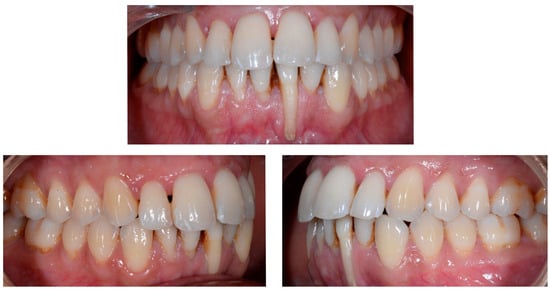

3.3. Severe Wire Syndrome

A 40-year-old patient presented with discomfort in tooth 31, citing past orthodontic treatment. As shown in Figure 11, the patient was in Class I and had poor oral hygiene associated with the presence of calculus in the incisivo-canine region. The root of 31, visible to its apex, was out of the bone and associated with severe gingival recession (Cairo RT2). Teeth 41 and 42 also showed gingival recession (Cairo RT2 and RT1).

Figure 11.

Severe wire syndrome. Frontal and lateral views.

Figure 12 and Figure 13 show a difference in the height of the free edges of the mandibular incisors and the extent of root visibility of 31.

Figure 12.

Severe wire syndrome. Frontal view.

Figure 13.

Severe wire syndrome. Lateral views.

No retainer was present in the maxilla, only a residual mandibular retainer, still bonded to 32 and 42, was visible (Figure 14), as well as incisal crowding and a difference in the visibility of the buccal and root surfaces of 41 compared to the contralaterals. In this extreme clinical situation, a severe and terminal wire syndrome on tooth 41, the “X-effect” type, was observed.

Figure 14.

Severe wire syndrome. Occlusal view.